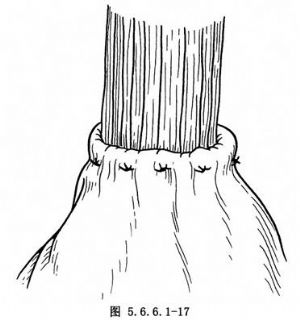

(4)常规食管胃端侧吻合:①先在预计切断食管的平面上方1cm处由食管边缘两侧分别用丝线穿过肌层与黏膜下层,与胃底部预计切开处的浆肌层缝合,两针之间的距离为食管的宽度(图5.6.6.1-10),图中食管壁上的虚线为准备切断食管的平面;②在两根缝线之间加缝数针,将食管后壁与胃底部浆肌层完全缝合(图5.6.6.1-11),图中胃壁上虚线为准备切开胃壁的部位;③切开胃壁浆肌层,但勿切透黏膜,将循行于黏膜下的每根血管用细丝线缝扎两处,然后在缝扎线之间切开胃黏膜。黏膜上切口开始不宜太大,在吻合过程中如嫌不足可再次切开(图5.6.6.1-12)。在切开胃壁之前应先用干纱垫置于吻合口后方以吸取切开胃黏膜后逸出的胃液,切开胃黏膜后迅速将吸引器头送入胃中吸净胃液;④沿预计切断食管的平面环绕食管切开肌层但勿切开黏膜,在食管肌层断面远侧约0.8cm的平面剪断食管黏膜,因留有足够的黏膜,吻合时十分便利,否则如在同一平面切断食管肌层及黏膜,由于后者的回缩使吻合操作相当困难;⑤将吻合口后壁食管全层的左右侧两角分别与胃壁切口的上缘全层用细丝线间断缝合,注意食管黏膜与胃黏膜必须对齐,缝线之间的间隔约为0.4cm,缝线结扎不能太紧以免术后局部组织水肿造成切割,成为发生吻合口瘘的主要因素(图5.6.6.1-13)。结扎线结打在腔内(图5.6.6.1-14);⑥将胃管经吻合口送入胃中,如果应用十二指肠饲食管,可在此时将引导饲食管的糖球一并送入胃中(图5.6.6.1-15),开始吻合前壁。由后壁转往前壁时,两侧转角处的缝线必须缝好,因在转角处容易发生瘘。吻合的最后4~5针最好先挂上线而不结扎,待全部缝合完毕时一次打结;⑦前壁第一层吻合完成以后,撤除原来置于吻合口后方的干纱布块,参加手术人员用无菌净水冲洗手套,将吻合使用过的器械前端用水洗净,用细丝线间断缝合吻合口前壁第二层,完成食管肌层及黏膜下层与胃底部浆肌层之间的缝合(图5.6.6.1-16);⑧将吻合口周围的胃壁用纱布向吻合口方向推送,结扎吻合口前壁第二层的缝线,使吻合口最后被套入胃壁中(图5.6.6.1-17);⑨将胃内引导十二指肠饲食管的糖球挤过幽门,清点台上敷料(包括纱布及纱垫)无误后,用中号丝线间断缝合膈肌。在胃越过膈肌处缝合不宜过紧,防止术后出现梗阻。将胃轻轻上推然后将胃壁与周围膈肌缝合6~7针,防止腹腔内脏器循此途径进入胸腔。注意不要用丝线将胃壁固定在胸壁上,此种缝线可能造成胃壁穿孔。如术者想采取措施减少吻合口的张力,可在近胃底部的胃大弯侧寻找一个切断大网膜的残结,用缝线穿过固定在纵隔胸膜上,同样可以达到吻合口减张的目的而无胃壁穿孔之虞。由第8肋间腋后线置入闭式引流管,检查胸内有无出血点或异物存留。用肋骨合并器将切口上下方的肋骨合拢,肋间组织用中号丝线缝合,冲洗胸壁肌肉,逐层关胸。将闭式引流管连接于水封瓶上。